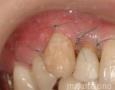

Pictures

7 Months